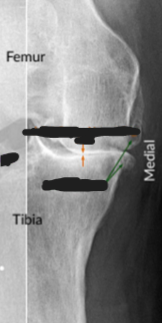

Osteoarthritis

Erosion of cartilage

Eburnation

Subchondral bone sclerosis

Fibrillation

Joint space is narrowed, but fusion (Ankylosis) does not occur

Subchondral bone sclerosis (Osteosclerosis)

Peripheral Osteophytes

Faint scattered radiolucent Subchondral Bone Cysts

Patellofemoral OA: Patella normally slides in the trochlear groove of the femur; cartilage along the trochlear groove & underside of the patella wear down

Knee OA: loss of cartilage in the Patellofemoral compartment or in the Lateral or Medial Tibiofemoral compartments

Sclerotic, dense bone

Joint space narrowed, but preserved